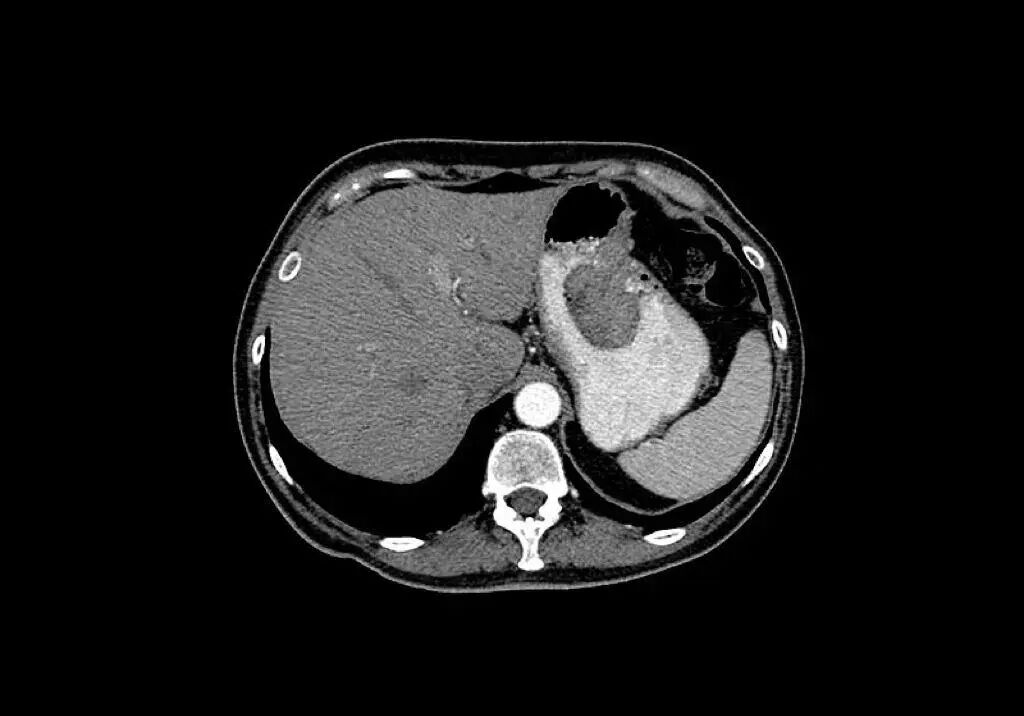

△胃癌CT扫描。